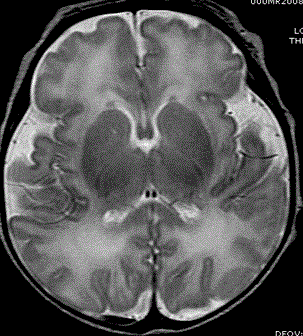

Структура (МРТ) головного мозга доношенного ребенка (фото любезно предоставлено RSNA).

Доктор Блёмль и его коллеги изучали недоношенных детей, чтобы узнать больше о том, каким образом преждевременные роды способны привести к изменениям в структуре мозга, которые могут быть связаны с клиническими трудностями в дальнейшей жизни. Большая часть внимания была сосредоточена на белом веществе мозга, которое ответственно за передачу сигналов и обеспечивает связь между различными частями мозга. Поскольку некоторые повреждения белого вещества видны при структурной магнитно-резонансной томографии (МРТ), группа доктора Блёмля использовала МР-спектроскопию (МРС), чтобы увидеть различия на микроскопическом уровне.

В этом исследовании ученые сравнили концентрации некоторых химических веществ, характеризующих полностью развитое белое и серое вещество у 51 доношенного ребенка и 30 недоношенных детей. Исследовательская группа получила нормальные результаты при структурной МРТ, но сканы МРС показали значительные различия в биохимическом развитии белого вещества у доношенных и недоношенных младенцев, что свидетельствует о нарушениях в сроках и синхронизации развития белого и серого вещества. Серое вещество является частью мозга, которая обрабатывает и передает сигналы. "У этих недоношенных детей схема развития мозга нарушается, — говорит доктор Блёмль. — Развитие белого вещества началось раньше и было "рассинхронизировано" с развитием серого вещества".